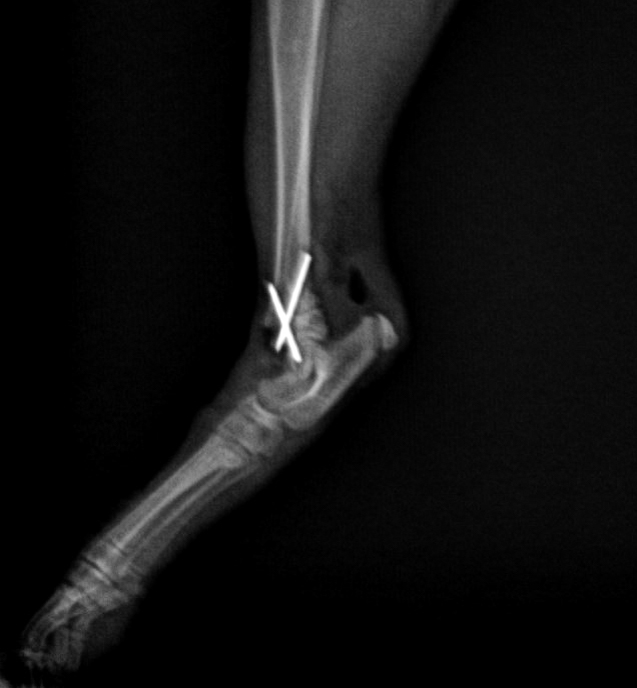

手術前後的X光片對比,手術前可見明顯骨折,手術用鋼釘固定骨折位置

辛巴穩定後,兩位醫生很快就替他進行手術。手術非常順利。他在康復期間恢復得非常快。現在他長大了一點,走路跑步沒有任何問題,非常活躍。最高興的是,他後來獲一位非常愛錫他的主人收養,命名為辛巴。